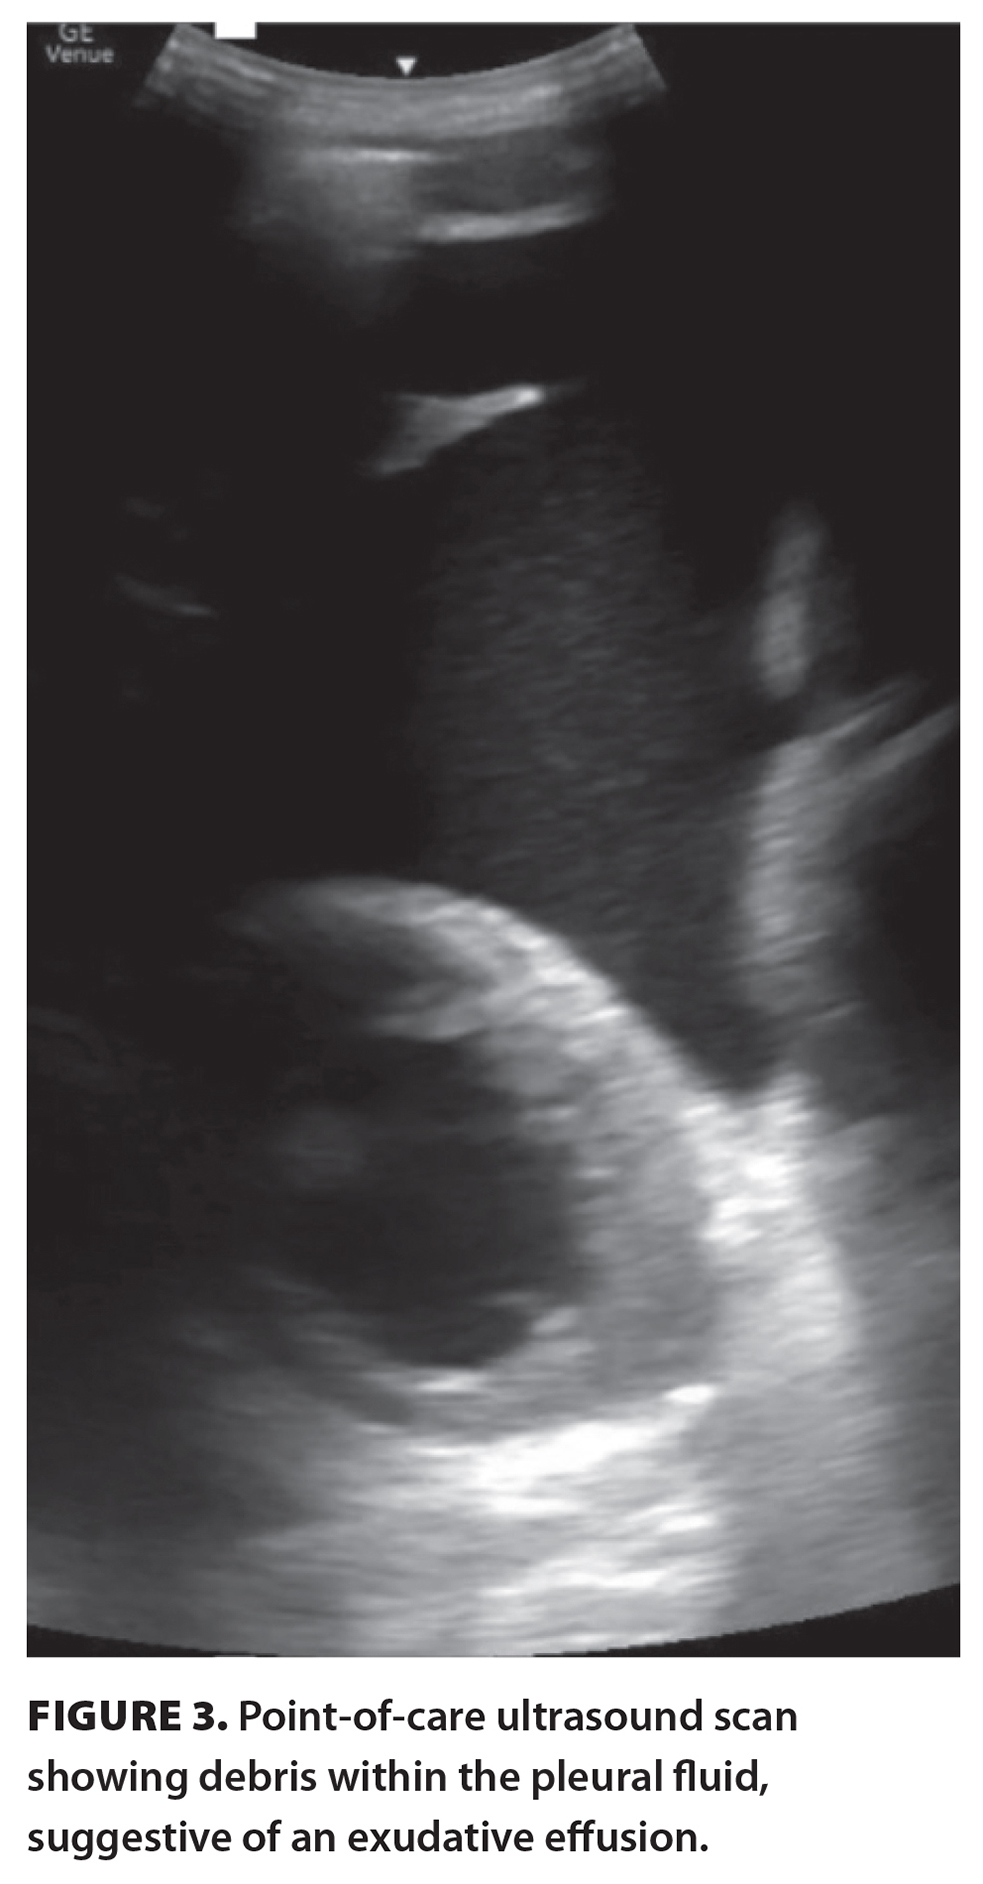

Given these findings, a diagnostic and therapeutic bedside point-of-care-ultrasound-guided thoracentesis was performed. The imaging revealed a bulky and ragged pleural membrane at the apex of the left lung, with a consolidated lung edge floating in a hypoechoic pocket of pleural effusion with evidence of swirling debris suggestive of an exudative process [Figure 3].